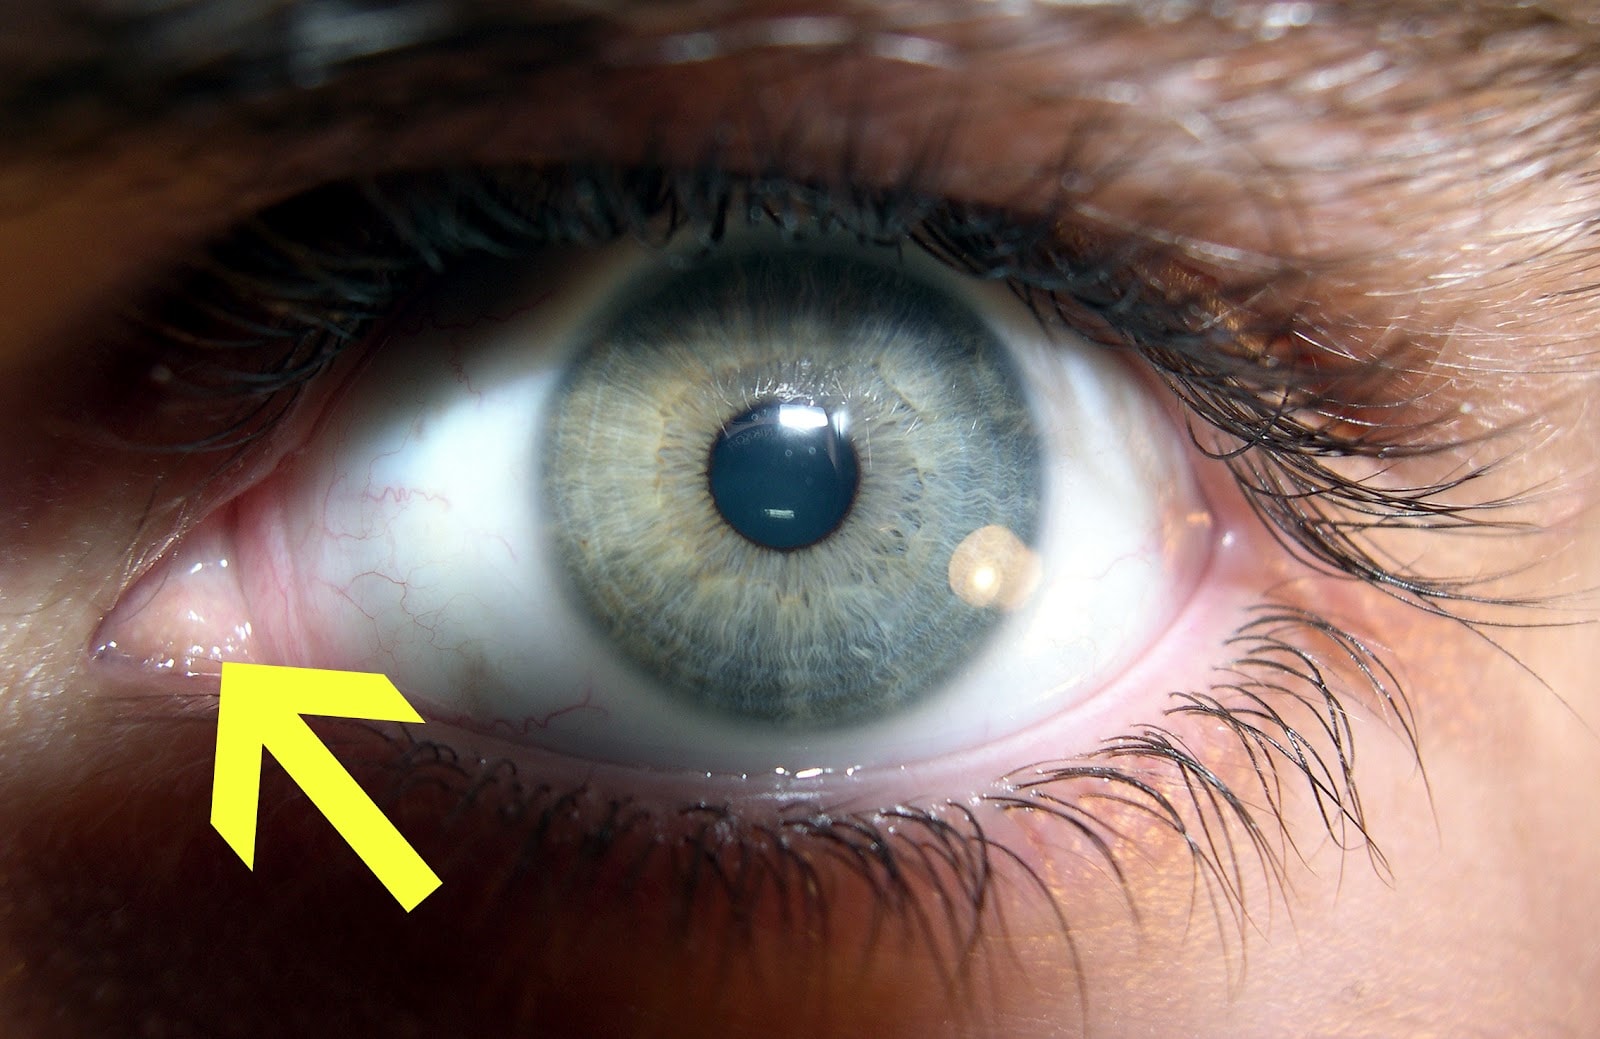

▼第三眼瞼:能夠保持眼睛濕潤,藉此來保護眼睛,並讓眼睛有著良好的視力,人類已經演化至只剩下一點,不過在一些鳥類和爬行類動物的眼睛中還是可以發現類似的薄膜。